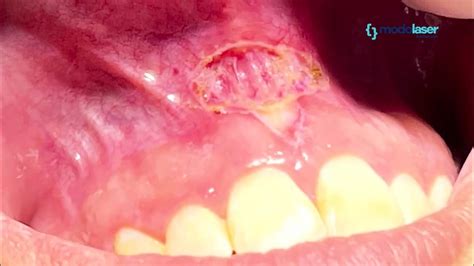

2. Frenectomía, operación del frenillo labial

Algunos diastemas se producen por la interferencia del frenillo labial superior. Para solucionar el espacio que existe entre los incisivos delanteros muchas veces solo se debe operar y disminuir el tamaño del frenillo llamada frenectomía.

Si un frenillo demasiado grueso es lo que separa dos dientes, la solución pasa por extirparlo mediante una cirugía muy sencilla.

En el caso del diastema provocado por el frenillo, la solución consistirá en una breve cirugía conocida como frenectomía. En ella se realiza un recorte del frenillo sobrante mediante un procedimiento rápido e indoloro.

La frenectomía es otro de los tratamientos que permiten solucionar un diastema. Es una cirugía muy sencilla y mínimamente invasiva que está indicada cuando los incisivos centrales superiores están separados debido a un frenillo labial demasiado grueso.

En estos casos, la frenectomía permite eliminar el exceso de tejido, lo que favorece que los dientes puedan juntarse. Sin embargo, para que esto ocurra será imprescindible realizar un tratamiento adicional.

La razón es que, una vez eliminado el exceso de frenillo, el espacio seguirá estando. Por tanto, habrá que completar el procedimiento con ortodoncia o carillas dentales.